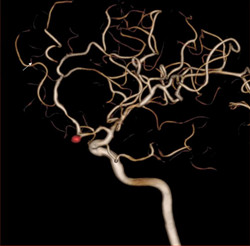

▲脑血管造影检查发现脑动脉瘤。

血管影像透明化技术让动脉结构一览无遗,更精准引导动脉瘤治疗。

▲前交通动脉瘤的血管造影图,红色一点被称为“定时炸弹”,

一旦破裂,死亡或病残率极高。